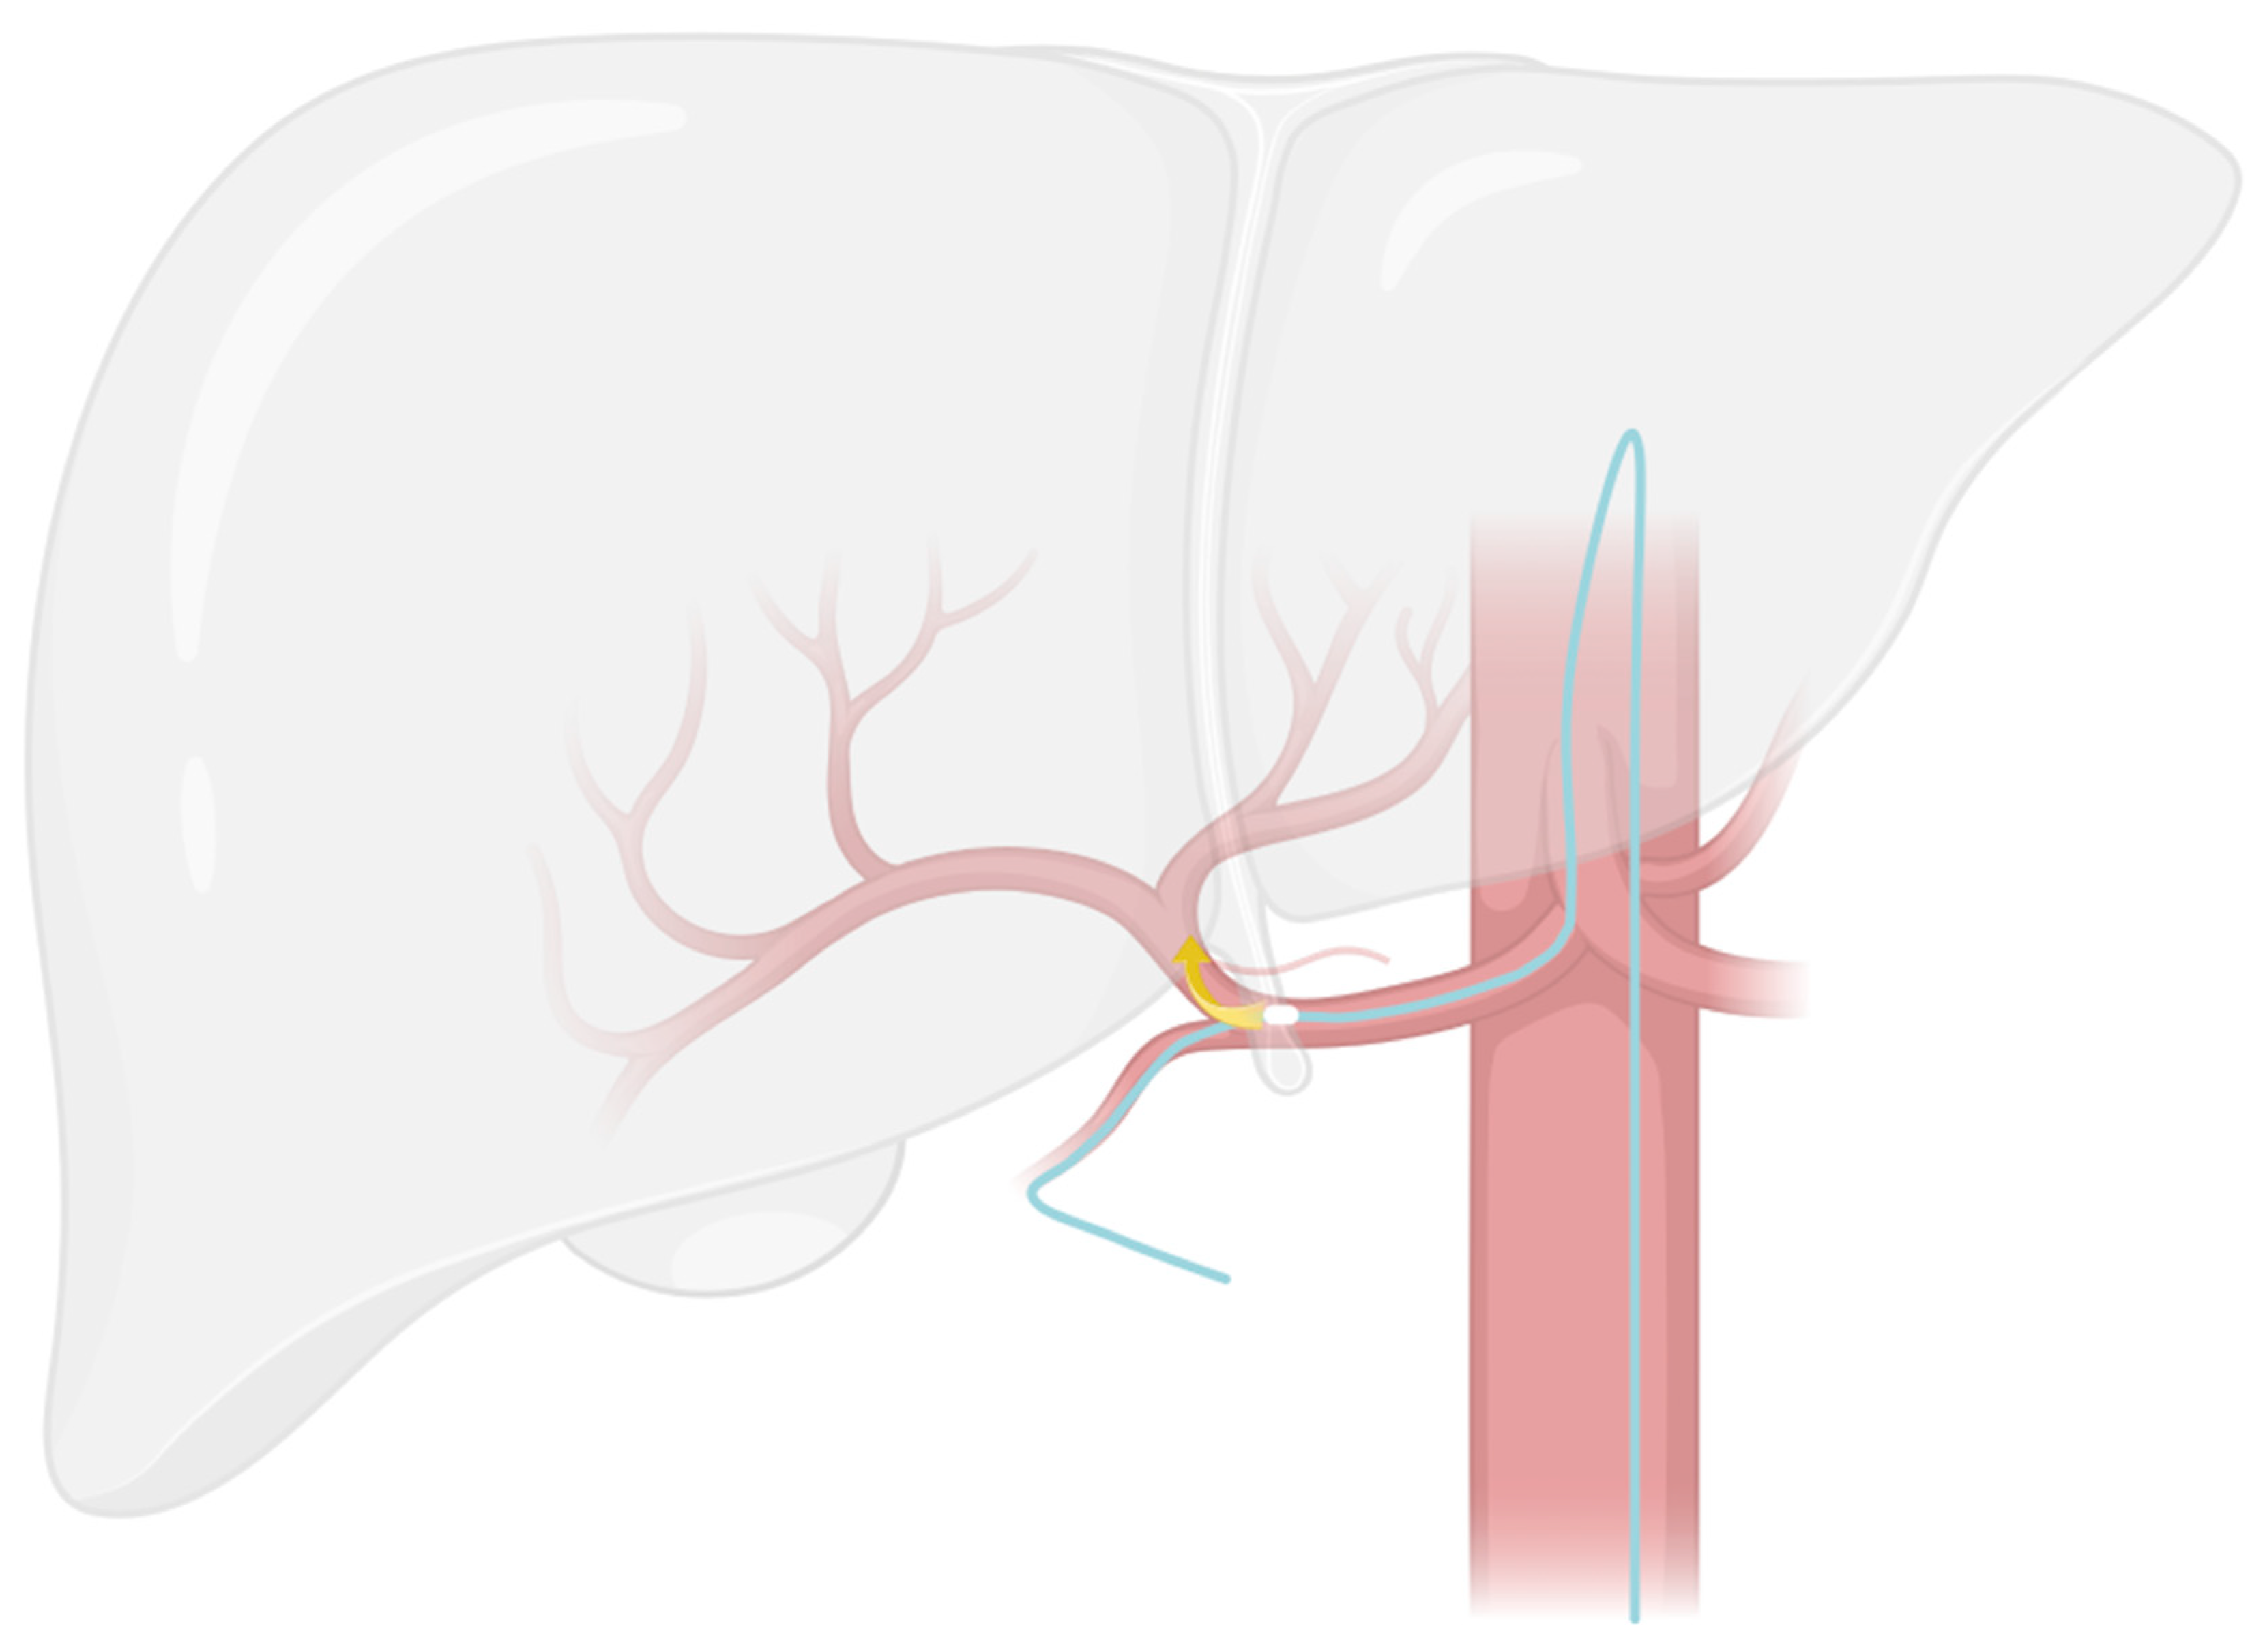

2.2. Modified Placement Technique

- The search for the optimal injection point.

- The skeletonization of the hepatic artery.